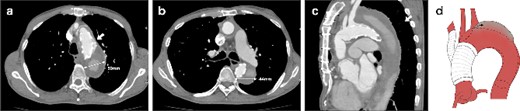

A 62-year-old male presented at the previous hospital with left hemiplegia. Computed tomography (CT) detected an aortic dissection with malperfusion of the right brachiocephalic artery, necessitating a referral to our institution. Preoperative CT showed the primary entry tear in the distal aortic arch and a patent false lumen. A total arch replacement was successfully performed using the fenestrated FET technique. The surgical procedure involved median sternotomy, establishment of extracorporeal circulation with right atrial drainage and perfusion via right axillary artery, circulatory arrest at 28°C and selective cerebral perfusion to perfuse all cervical vessels. Myocardial protection was provided by retrograde cardioplegia. Following resection of the aorta at zone 1, FET was inserted and deployed into the aorta, perfusing blood from the femoral artery. Fenestration of the graft at the ostium of the second and third cervical branches was performed. A U-shaped graft was placed around cervical branches, and three 4-0 polypropylene U-shaped sutures were roughly placed to fix the open stent graft, leaving some gaps between the sutures. Subsequent procedures included anastomosis of a four-branch graft to the distal aorta, reconstruction of the brachiocephalic artery and proximal anastomosis. Postoperative contrast-enhanced CT on day 5 showed no endoleak and favorable remodeling of the descending aorta (Fig. 1). However, after 6 months, follow-up CT detected a fenestration-related endoleak and an enlarged aortic arch (Fig. 2), prompting reoperation. The reoperation involved median re-sternotomy, establishment of extracorporeal circulation with right femoral vein drainage and perfusion via an 8-mm graft anastomosed to the left axillary artery, circulatory arrest at 28°C, and selective cerebral perfusion to perfuse all cervical vessels. Upon opening the artificial graft, it was observed that the stent graft had some gap between fixed U-sutures and had become detached from the aorta, revealing a small entry adjacent to it, which communicated with the false lumen. The left subclavian artery (LSCA) was ligated, and the left common carotid artery was transected at its origin and sutured. An open stent was inserted distally, followed by placement of a felt strip and a 4-0 running suture. Subsequent procedures included anastomosis of a four-branch graft to the distal aorta, reconstruction of the three cervical branches and proximal anastomosis. The surgery was completed without complications. Postoperative contrast-enhanced CT on day 5 revealed resolution of the endoleak with no blood flow into the false lumen of the arch. Follow-up CT 3 months after discharge revealed favorable remodeling of the aortic arch (Fig. 3).

CT 6 months after the initial surgery reveals an endoleak from the fenestration (indicated by the white arrow), antegrade flow in the false lumen, and an enlarged aorta at the levels of the aortic arch (a) and the carina of the trachea (b). Sagittal image (c). An illustrative diagram (d) shows the schema of endoleak from fenestration (indicated by the black arrow).